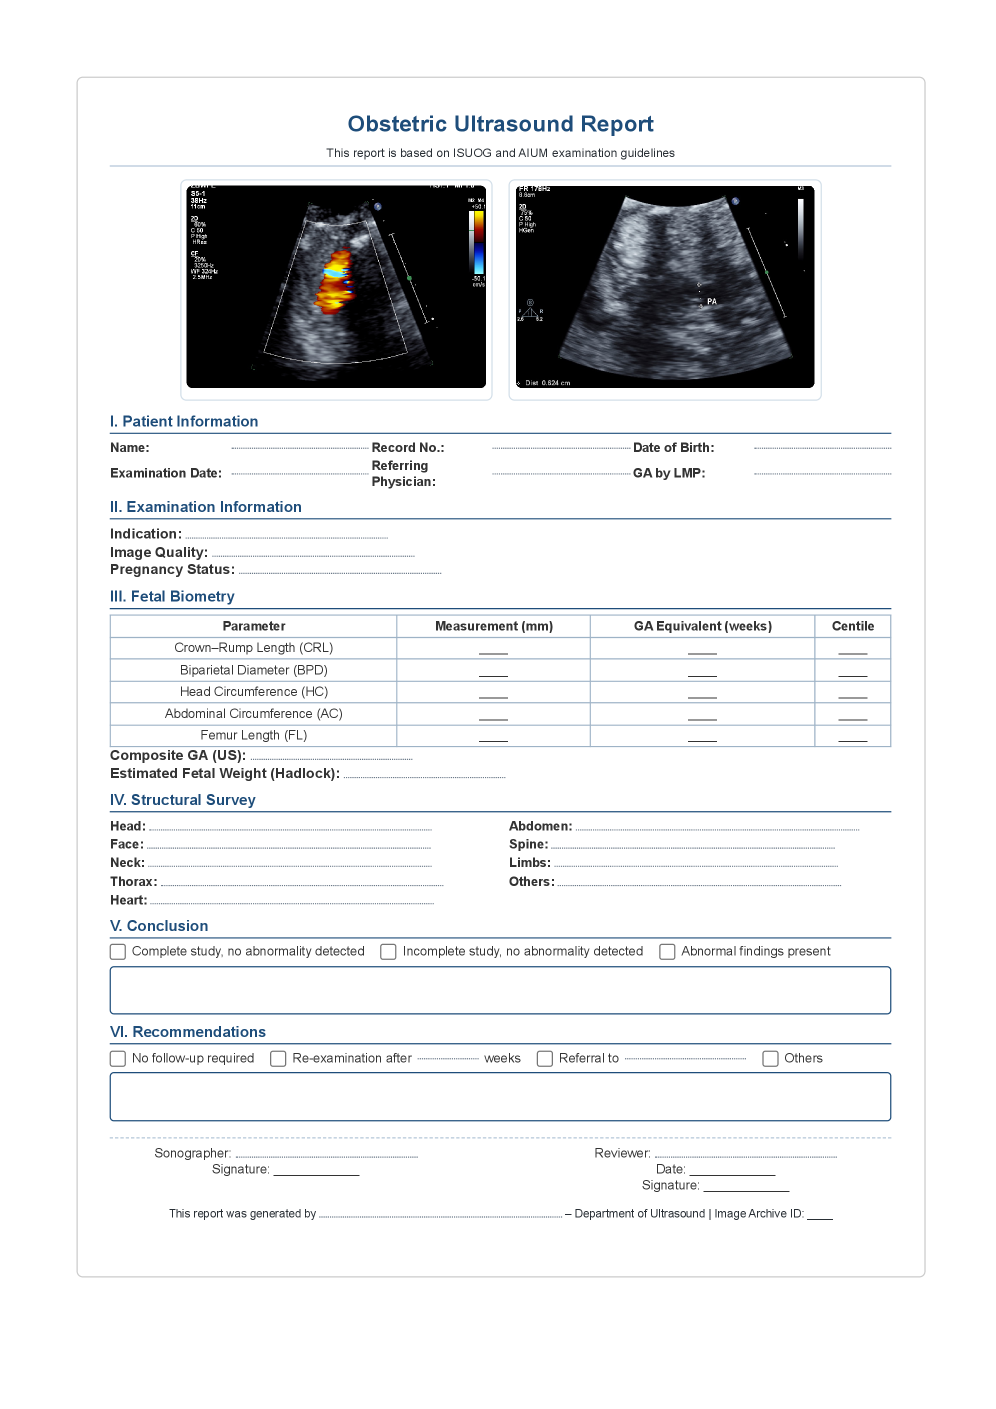

In this appendix, we provide supplementary material to further elucidate our approach. Appendix A expands on the experiments with detailed protocols and ablation studies. Appendix B introduces the preliminaries of the Salient Epistemic Disentanglement (SED) reinforcement learning module. Appendix C visualizes the standardized structured report template that guides fetal ultrasound report generation and diagnosis. Finally, Appendix D consolidates the evaluation metrics and their definitions used throughout the paper.

To promote both clinical validity and cross-center consistency, we constructed a standardized obstetric ultrasound report template by systematically consolidating and harmonizing recommendations from multiple international guidelines, including those issued by the ISUOG, AIUM, and Chinese Medical Association. As illustrated in Figure 13 and Figure 14, we release both an English and a Chinese version of the template. The English version facilitates alignment with widely adopted global standards, while the Chinese version ensures applicability in large-scale domestic clinical practice. Together, these templates provide a unified and clinically grounded structure for report writing, enabling reliable data annotation, model training, and evaluation. Importantly, by establishing a guideline-based framework, the templates mitigate variability across institutions and languages, offering a scalable foundation for developing deep learning systems that generalize robustly across centers, devices, and populations.